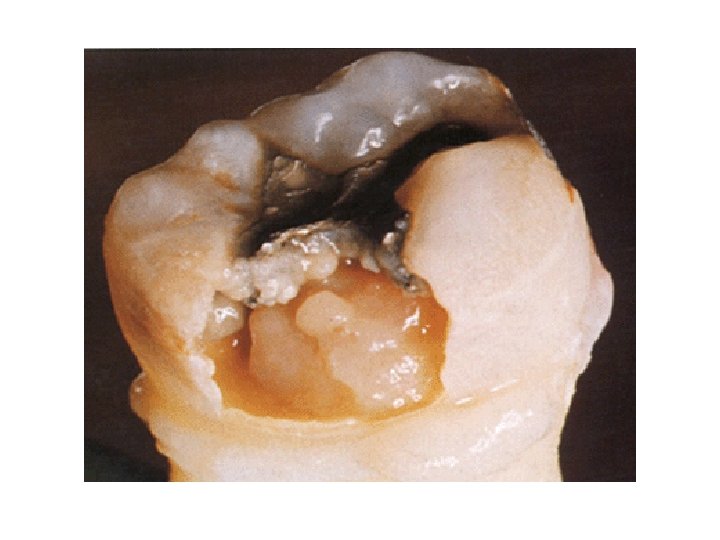

CARIES OF DENTIN • Initial penetration of dentin by caries may result in dentinal sclerosis • This is a reaction of vital dentinal tubules and a vital pulp, in which results in calcification of dentinal tubules, that tend to seal them off against further penetration by microorganisms • The different zones which are present in carious dentin are (beginning pulpally at advancing edge of lesion) Zone 1 : zone of fatty degeneration of Tome’s fibres Zone 2 : zone of degeneration Zone 3 : zone of decalcification Zone 4 : zone of bacterial invasion of decalcified but intact dentin Zone 5 : zone of decomposed dentin